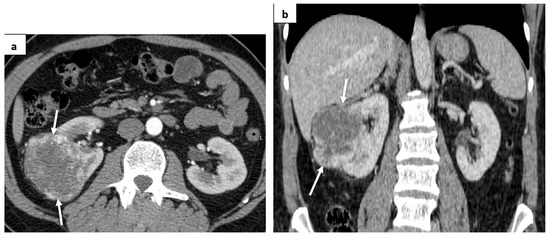

2. Case Report